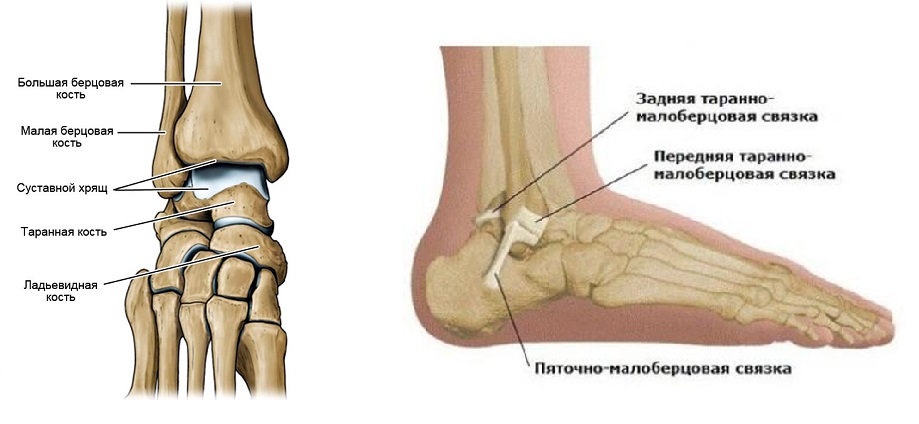

Анатомические фото голеностопного сустава и его суставных поверхностей